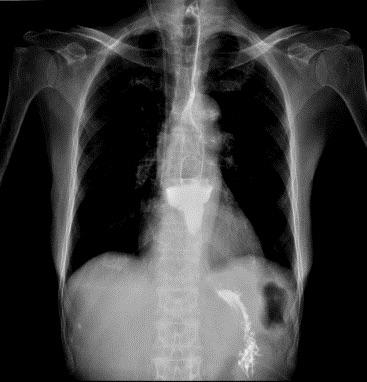

赵奶奶听了钟教授的病情解释后,恳请钟教授尽快手术。钟教授当天就安排赵奶奶住院检查,行术前评估,次日就给赵奶奶完成了内镜下微创手术:隧道内镜下食管憩室嵴切开术。钟教授运用内镜电刀在食管憩室上方建立“隧道”入口,打通“隧道”,在“隧道”内暴露出憩室嵴,最后应用内镜刀切开憩室嵴肌肉,在食管腔观察憩室嵴消失,金属夹关闭“隧道”入口。手术顺利,整个手术过程仅仅用时30分钟。术后复查造影,造影剂流出食管顺畅,不再潴留于食管憩室。赵奶奶术后经过禁食、胃肠减压、抑酸、营养支持等治疗,1天后进食流质饮食无明显不适,未再呕吐。术后逐步增加饮食,赵奶奶也未再呕吐,并且体重逐步增加,精神越来越好。就这样,困扰了赵奶奶好多年的呕吐,竟然这么快就治好了。

图2  食管憩室,术后憩室嵴消失,造影剂顺畅流出食管